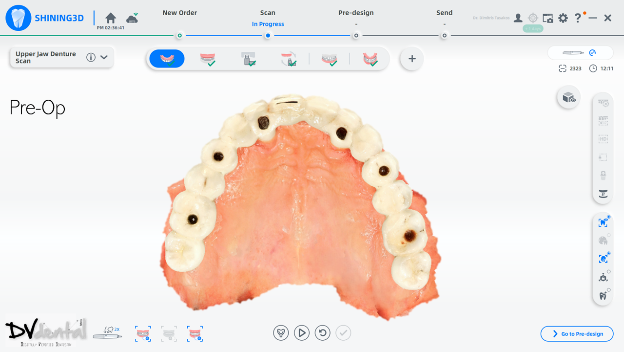

Fig 4: First step, scan the Pre-op scan to capture the old restoration

In this case, we encountered a problem: while the MUA of the four anterior implants were compatible with the IPG scan bodies, the two posterior implants were not compatible with the IPG scan bodies. Therefore, we will scan the two posterior implants using normal 3D reconstruction technology (in the soft tissue scan, placing two standard scan bodies on the MUA of the two posterior implants) and then scan the anterior implants with IPG technology (placing the IPG scan bodies on the MUA of the four anterior implants).